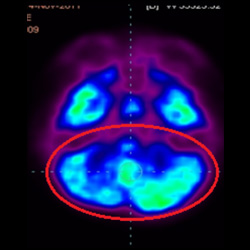

細胞治療后,藍色和黑色區域減少,并且看到更活躍的區域。這表明損傷減少并改善了大腦功能。

這證明細胞療法是治療腦癱兒童安全有效的方法。細胞療法可以更新大腦損傷的核心,并且可以通過 PET CT 掃描來監測大腦的改善情況。這些細胞療法與標準治療一起促進腦癱兒童的生長和改善。